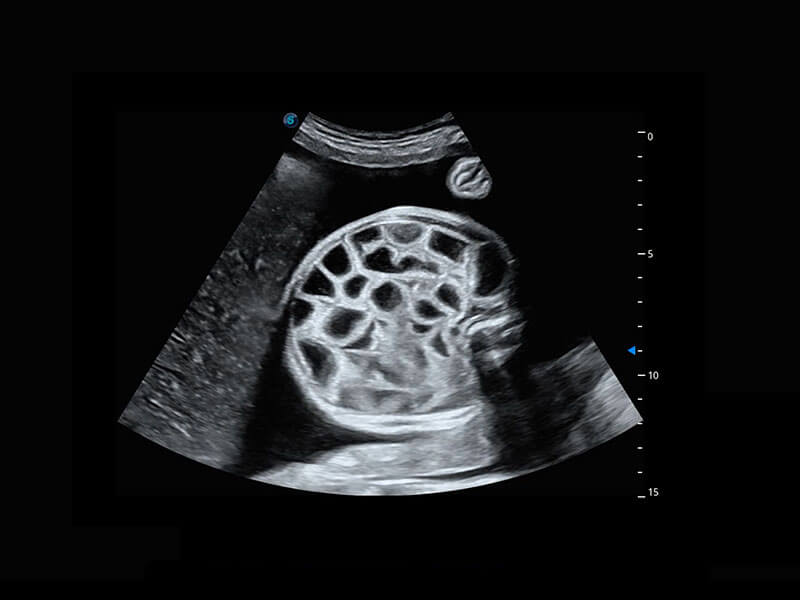

中晚孕筛查

P60提供简单易学易用的高端诊断工具,为您中晚孕筛查提供快速清晰的解剖信息。

1 OFD(HC): 87.03 mm

HC: 251.00 mm

GA: 27w 1d

HC/AC: 96.13 %

2 BPD: 70.56 mm

GA: 28 w 2d